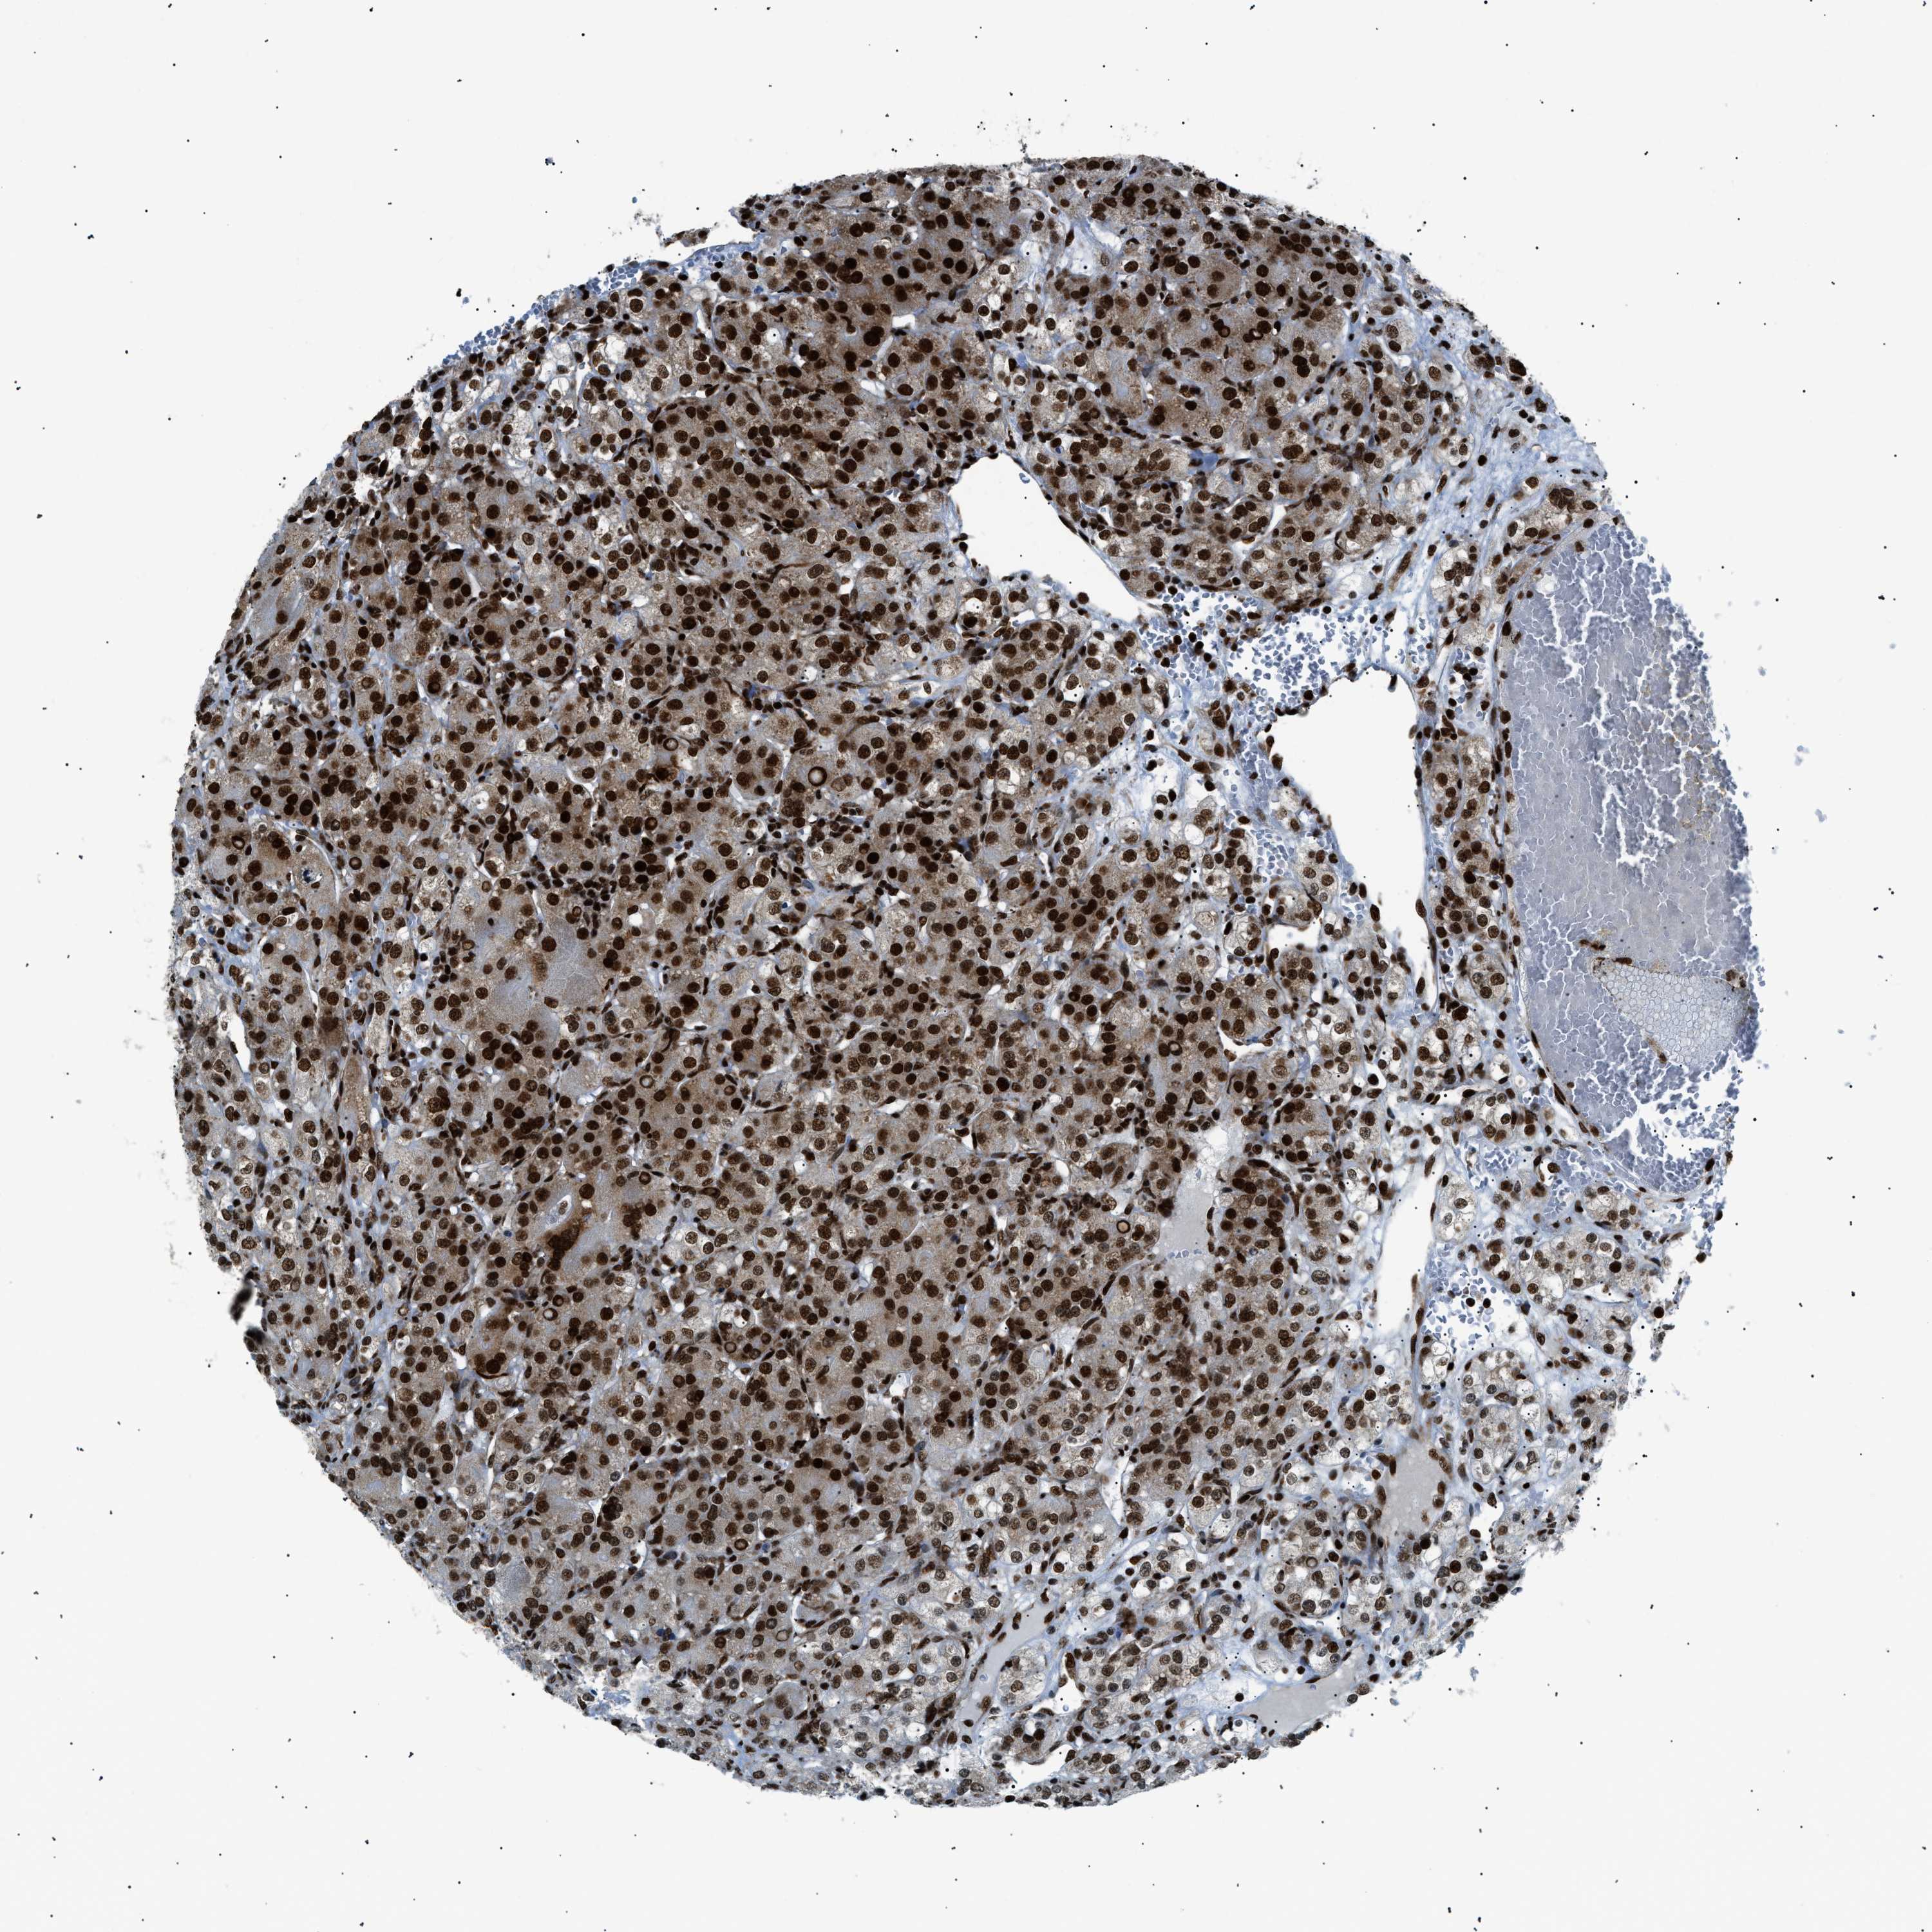

HNRNPK is validated prognostic, high expression is favorable in Kidney Renal Clear Cell Carcinoma (TCGA)

Best expression cut offi

Based on the FPKM value of each gene, patients were classified into two groups and association between prognosis (survival) and gene expression (FPKM) was examined. The best expression cut-off refers the FPKM value that yields maximal difference with regard to survival between the two groups at the lowest log-rank P-value. Best expression cut-off was selected based on survival analysis .

When clicking on this number, the vertical dashed line indicating cut-off, the interactive survival plot, and the Kaplan-Meier curve will be adjusted to show results based on the best expression cut-off.

: 263.23

TCGA RNA samplesi

RNA-seq data is reported as average FPKM (number Fragments Per Kilobase of exon per Million reads), generated by the The Cancer Genome Atlas (TCGA) .

Normal distribution across the dataset is visualized with box plots, shown as median and 25th and 75th percentiles. Points are displayed as outliers if they are above or below 1.5 times the interquartile range. FPKM values of the individual samples are presented next to the box plot.

Average pTPM 336.9

Number of samples 521